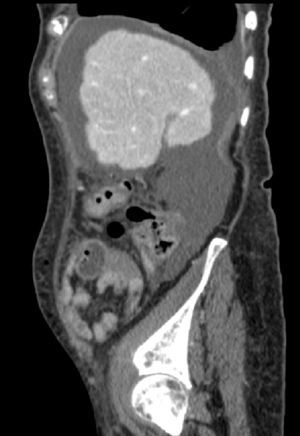

Caso 2Mujer de 78 años con mastectomía, prótesis mitral mecánica, hipotiroidismo, hepatopatía no filiada, insuficiencia tricuspídea, FA crónica en tratamiento con digoxina y acenocumarol, que precisó un resección anterior baja tras diagnosticarse un adenocarcinoma en la unión rectosigmoidea. En la analítica preoperatoria destacaba una creatinina de 1mg/dl. Las transaminasas eran normales y la bilirrubina de 1,2mg/dl. En el hemograma se observaba anemia microcítica con hemoglobina: 10,2g/dl. La paciente fue intervenida con los parámetros de hemostasia correctos y no presentó sangrado intraoperatorio. Durante la operación se observó una cirrosis avanzada sin ascitis ni circulación colateral significativa en el territorio esplácnico. El catéter epidural y el drenaje fueron retirados antes de las 48h poscirugía y se reiniciaron dosis terapéuticas de enoxaparina al 4.° día de la intervención (1mg/kg peso/12h). La paciente fue dada de alta al 6.° día postoperatorio tras una recuperación extraordinaria con reanudación del tránsito intestinal y buena tolerancia a la dieta blanda. Al día siguiente, acudió a urgencias del hospital por la noche tras presentar dolor abdominal agudo. Se realizó un TC abdominal, observando un gran hematoma (fig. 1) y la paciente fue intervenida de madrugada, evacuando 2.000cc de sangre. Posteriormente, la enferma presentó buena evolución y fue tratada satisfactoriamente con HBPM a bajas dosis (<1mg/kg peso/día) hasta reanudar de nuevo la anticoagulación oral.